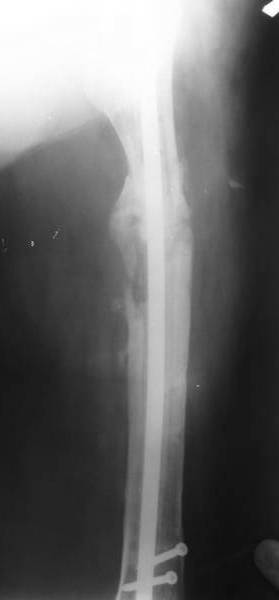

В настоящее время наш пациент ( см. http://weborto.net/forum/1177351385/index_html) ходит с одним костылем. У него периодически открывается свищ на задне-наружной поверхности бедра с умеренным серозно-гнойным отделяемым. Температура тела и анализы нормальные. На рентгенограммах имеются признаки консолидации ложного сустава.

1, 2, 3, 4 - рентгенограммы бедра от 8 августа этого года (через четыре месяца после операции);